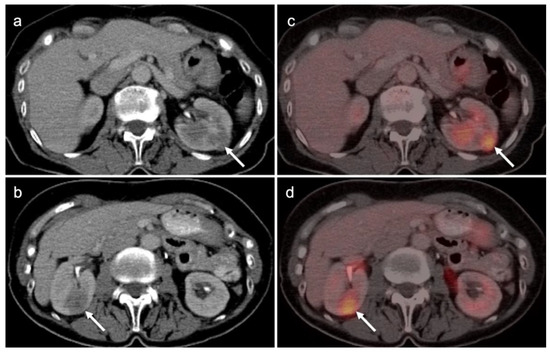

3.2. Urothelial Carcinoma